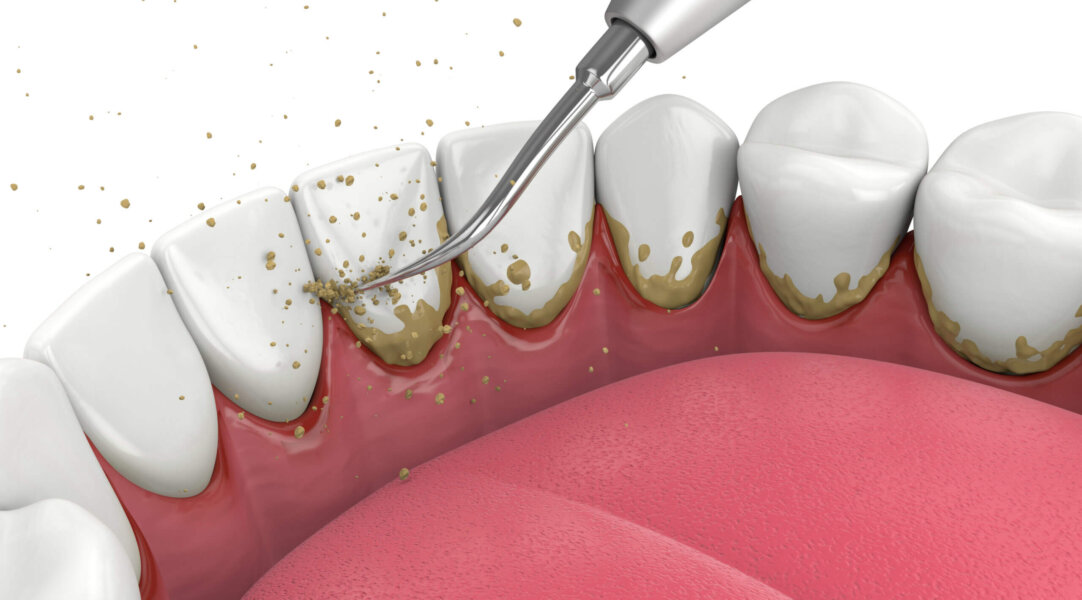

স্কেলিং কী?

স্কেলিং হলো একটি ডেন্টাল প্রক্রিয়া যার মাধ্যমে দাঁতের উপর জমে থাকা প্লাক (plaque) এবং টার্টার (tartar) দূর করা হয়। প্লাক হলো একটি পাতলা ব্যাকটেরিয়া স্তর যা দাঁতের উপর জমে থাকে, আর টার্টার হলো প্লাকের কঠিনীকৃত রূপ। নিয়মিত স্কেলিং করলে:

- স্কেলিং প্রক্রিয়া:

- আল্ট্রাসোনিক বা ম্যানুয়াল টুল ব্যবহার করে প্লাক ও টার্টার দূর করা হয়।

- দাঁতের উপরের ও নিচের অংশ সব পরিষ্কার করা হয়।